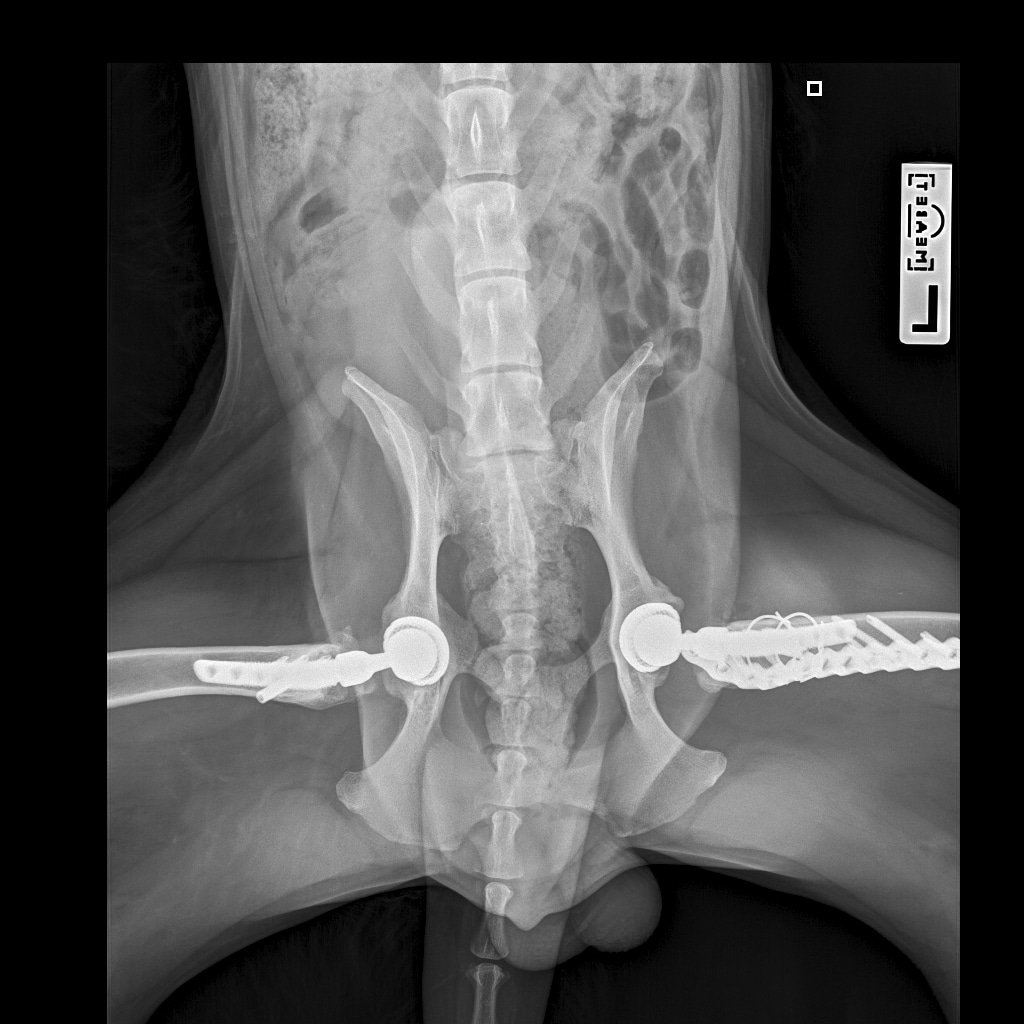

26 августа к 10 утра голодными, нас ждут на контрольный рентген в клинике на Вернадского.

Рентген будет под седацией

За время противовоспалительной терапии снизилось воспаление и в левом тазобедренном суставе, но увы, форма головки бедренной кости и состояние шейки бедра , лучше не стали:(((

Операция однозначно нужна.

Снимки столь качественные, что их можно в учебник